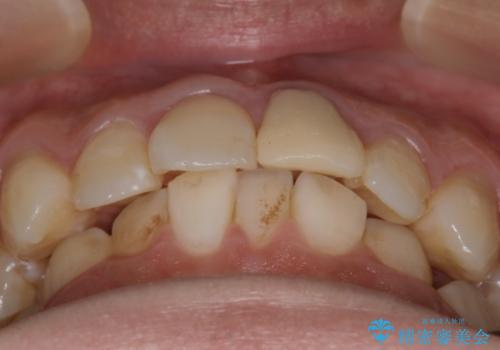

- 前歯のがたつきと口元を下げたいとのことで来院されました。

骨格的に左右差があるので正中を合わせることと抜歯矯正での口元改善は難しいことを説明させていただきました。

インビザラインにて治療を行うことで、前歯のがたつきが改善されました。

左上1番目の前歯はセラミックをご希望されたので、セラミックにて被せ物の治療を行いました。

とても綺麗な前歯になりました。